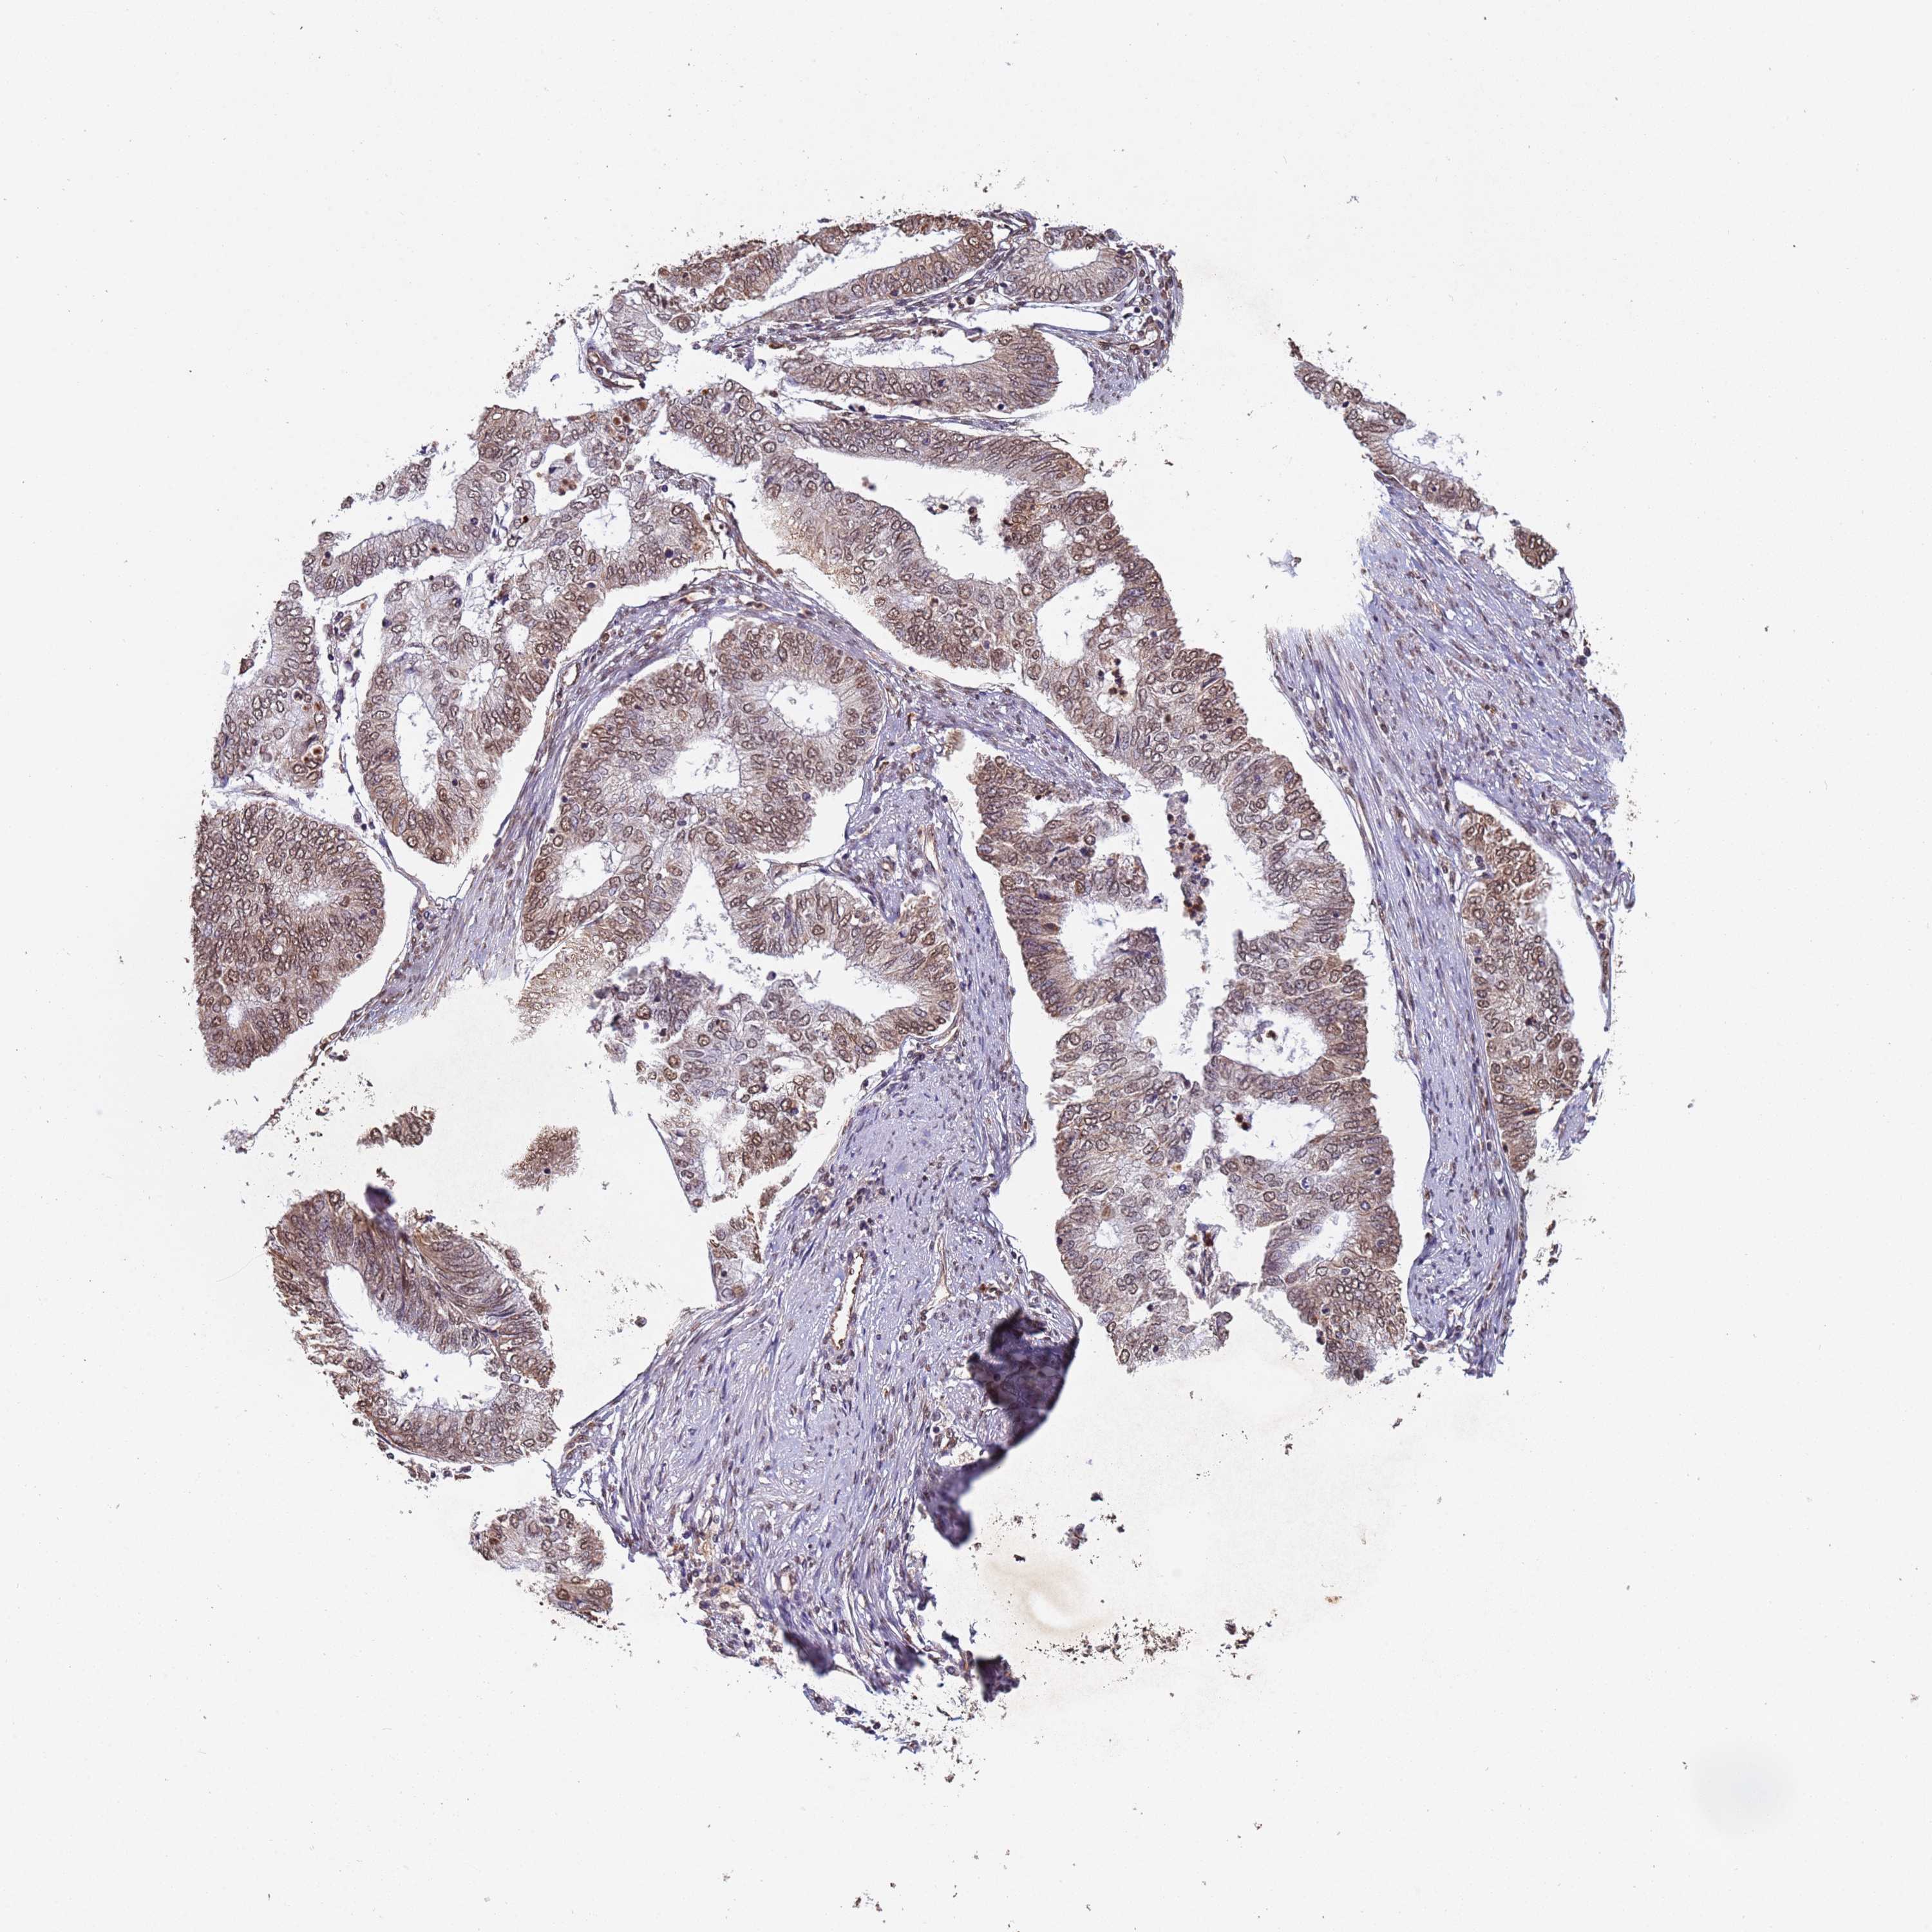

ENDOMETRIAL CANCER - Protein expressioni

A mouse-over function shows sample information and annotation data. Click on an image to view it in a full screen mode. Samples can be filtered based on level of antibody staining by selecting one or several of the following categories: high, medium, low and not detected. The assay and annotation is described here.

Note that samples used for immunohistochemistry by the Human Protein Atlas do not correspond to samples in the TCGA dataset.

Antibody stainingi

Antibody staining in the annotated cell types in the current human tissue is reported as not detected, low, medium, or high, based on conventional immunohistochemistry profiling in selected tissues. This score is based on the combination of the staining intensity and fraction of stained cells.

Each image is clickable and will lead to virtual microscopy that enables deeper exploration of all samples and also displays staining intensity scores, fraction scores and subcellular localization as well as patient and tissue information for each sample.

Antibody HPA045624

Staining

High

Medium

Low

Not detected

Intensity

Strong

Moderate

Weak

Negative

Quantity

>75%

75%-25%

<25%

None

Location

Nuclear

Cytoplasmic/membranous

Cytoplasmic/membranous,nuclear

Adenocarcinoma, NOS